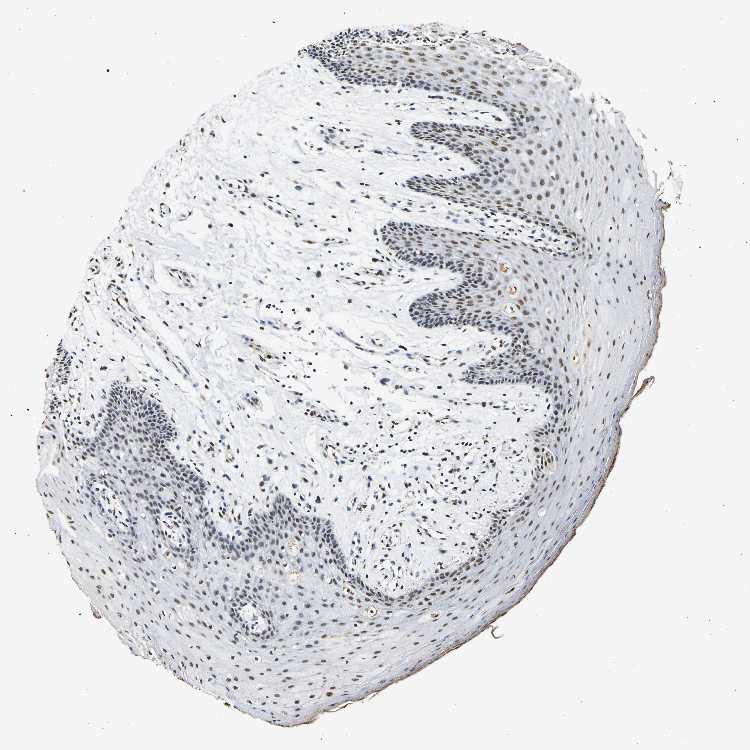

TISSUE PRIMARY DATA ORAL MUCOSA Show tissue menu

ORAL MUCOSA - Antibody stainingi

Antibody staining in the annotated cell types in the current human tissue is reported as not detected, low, medium, or high, based on conventional immunohistochemistry profiling in selected tissues. This score is based on the combination of the staining intensity and fraction of stained cells.

Each image is clickable and will lead to virtual microscopy that enables deeper exploration of all samples and also displays staining intensity scores, fraction scores and subcellular localization as well as patient and tissue information for each sample.

Antibody HPA016832Antibody HPA020076Antibody CAB001969

Squamous epithelial cells HighHighHigh